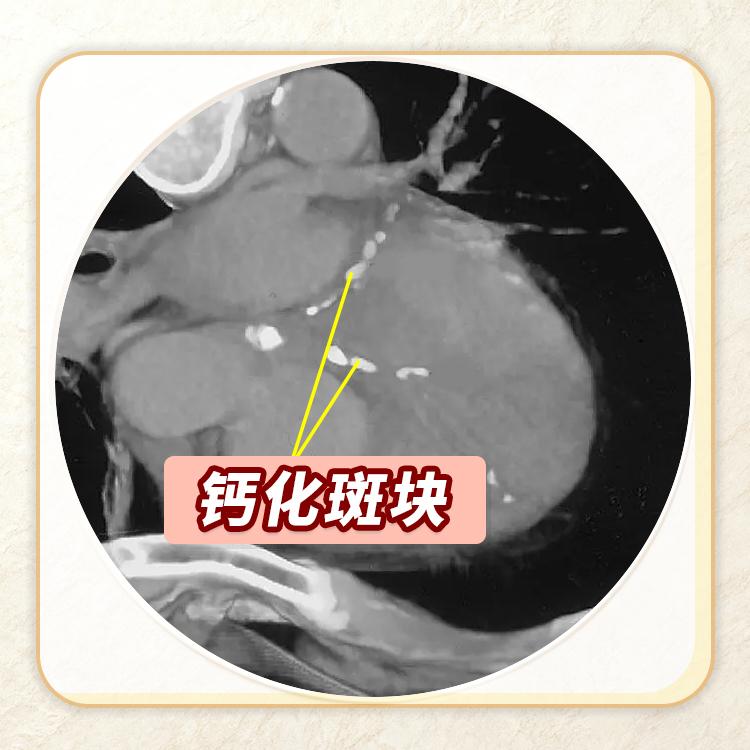

一、钙化斑块

在CT图像上,软组织密度低呈灰色,而钙化病变则像一颗颗小石子一样,密度特别高,就会显现白色。

血管上的斑块就像是水管里的水垢。刚开始血管壁长的斑块是“软斑块”,学名叫非钙化斑块,主要是脂肪、细胞等成分;随着时间推移,这些软斑块会沉积钙质,逐渐变硬,成为钙化斑块。钙化斑块在CT图像中表现为一个个小白点,提示血管存在动脉硬化。

钙化斑块虽然“硬”,但相对安全:它像血管上的瘢痕,结实且不容易破,也不易形成血栓,但目前没有药物能把它去掉,一旦发现就提示有动脉硬化,需要关注整体血管健康。